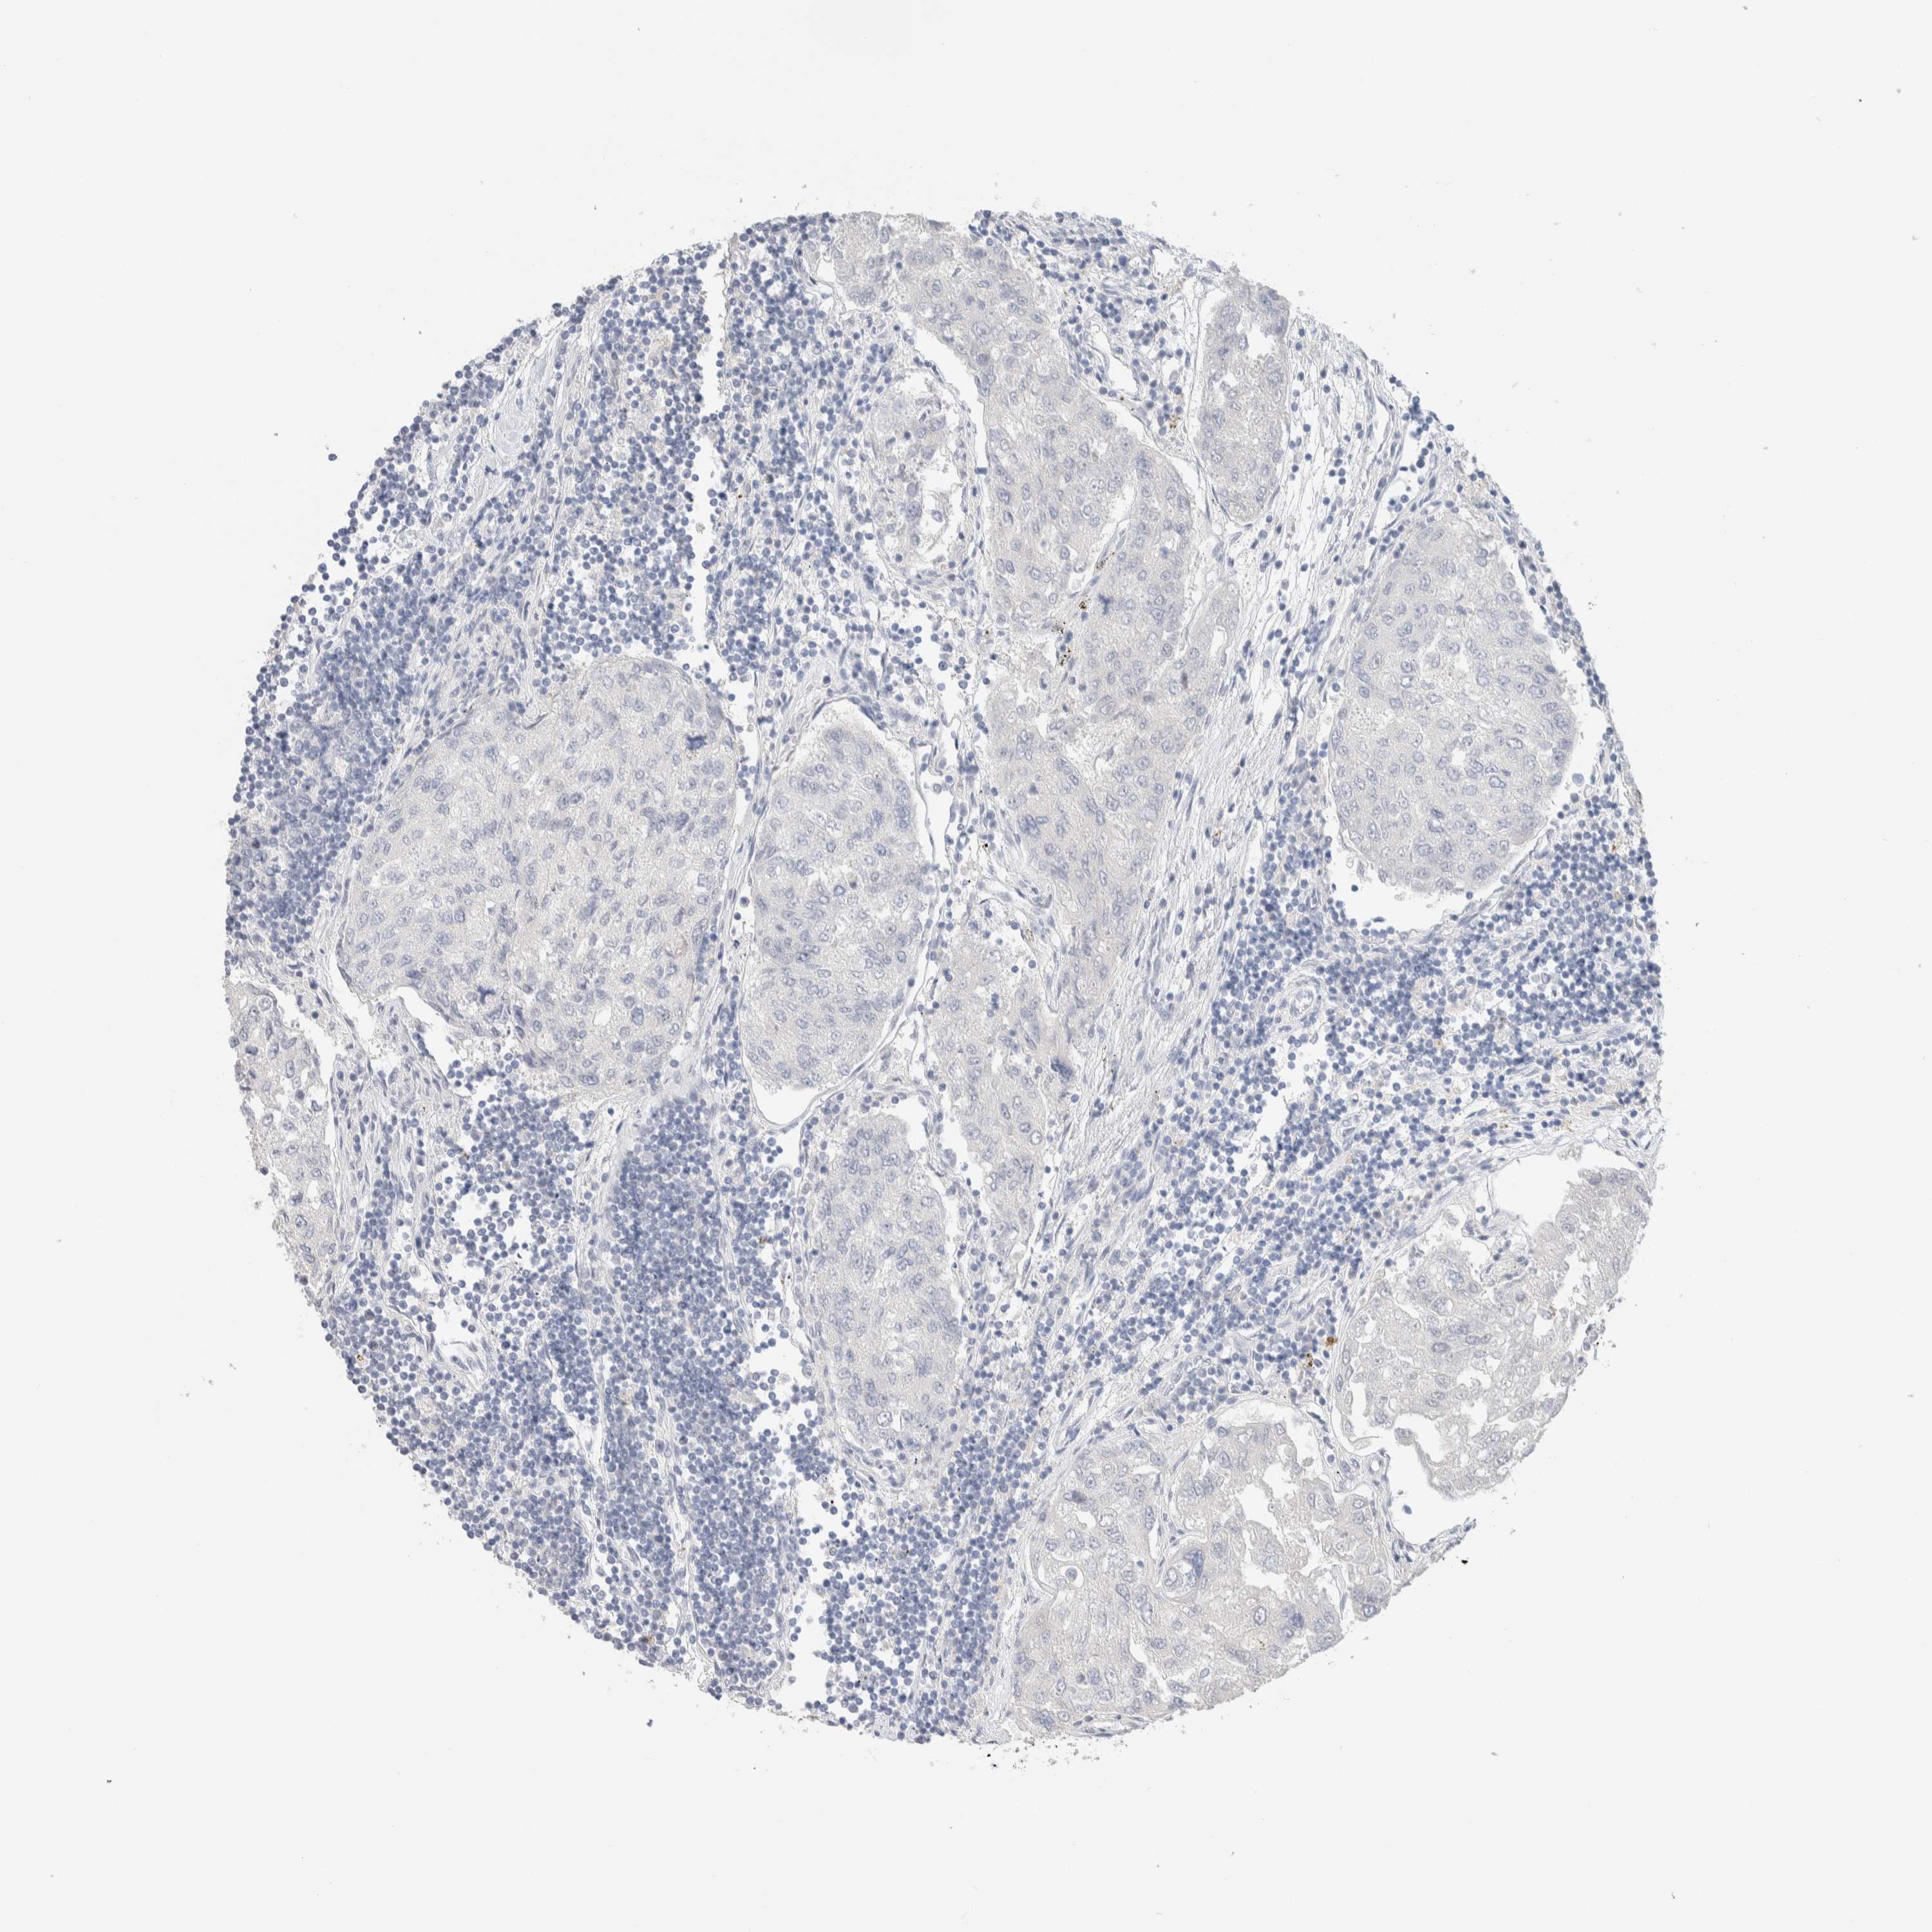

UROTHELIAL CANCER - Protein expressioni

A mouse-over function shows sample information and annotation data. Click on an image to view it in a full screen mode. Samples can be filtered based on level of antibody staining by selecting one or several of the following categories: high, medium, low and not detected. The assay and annotation is described here.

Note that samples used for immunohistochemistry by the Human Protein Atlas do not correspond to samples in the TCGA dataset.

Antibody stainingi

Antibody staining in the annotated cell types in the current human tissue is reported as not detected, low, medium, or high, based on conventional immunohistochemistry profiling in selected tissues. This score is based on the combination of the staining intensity and fraction of stained cells.

Each image is clickable and will lead to virtual microscopy that enables deeper exploration of all samples and also displays staining intensity scores, fraction scores and subcellular localization as well as patient and tissue information for each sample.

Antibody HPA022856

Antibody HPA023489

Urothelial carcinoma, Low grade

Urothelial carcinoma, High grade